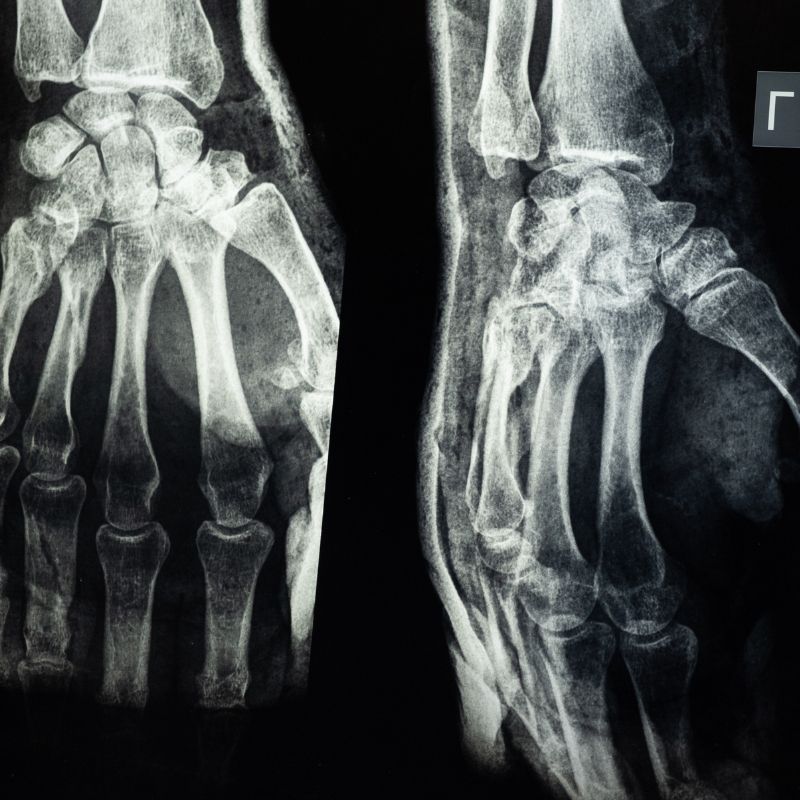

• Left wrist fracture

The collision severely diminished the couple’s quality of life.  The elderly woman reported that her hand is stiff and swollen, as if it has been ‘smashed’ – and has experienced an inability to hold objects without dropping them.  She has suffered emotional difficulties, fatigue, and constant pain.  She has been unable to continue participating in activities from which she previously derived meaning and joy, including exercise, self-care, and housekeeping.  The elderly man struggled to balance while standing.  He had difficulties sleeping, which caused constant fatigue.  Simply having a conversation with other people became nearly impossible, as he could not maintain the necessary focus and attention.  For the final years of his life, he experienced constant low mood and motivation, and high levels of stress, anger, sadness, and anxiety.